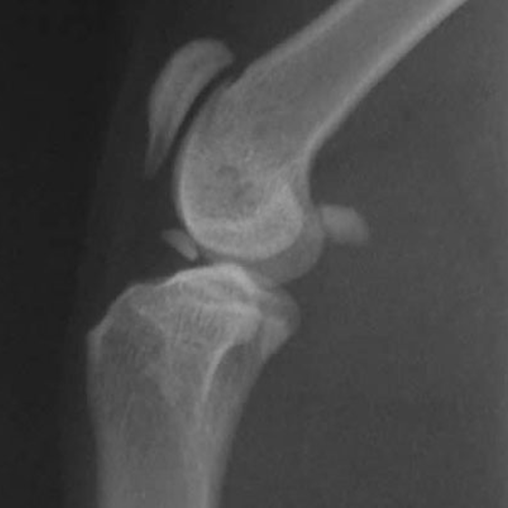

Panosteitis in a GSD puppy